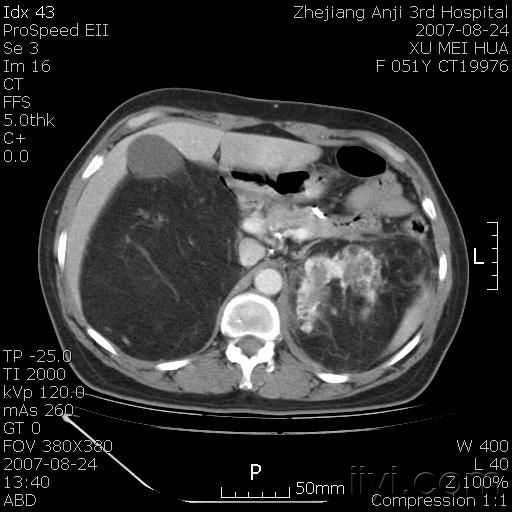

以下是引用还珠格格在2007-8-27 10:19:00的发言:[br]双侧肾脏形态失常,可见巨大的以低密度脂肪为主的混合性肿块,占据中下腹,残留的肾组织轻度强化,增强后肿块内实质部分呈峰窝状强化,低密度区无强化。另左侧肾盂轻度积水。根据病史 考虑 双肾血管平滑肌脂肪瘤可能性大。[br] 鉴别诊断 1、脂肪瘤,境界清楚,肿块内完全是脂肪,几乎没有软组织成分; 2、畸胎瘤:罕见,除有软组织成分外,另一特征是有钙化或骨化影组织。